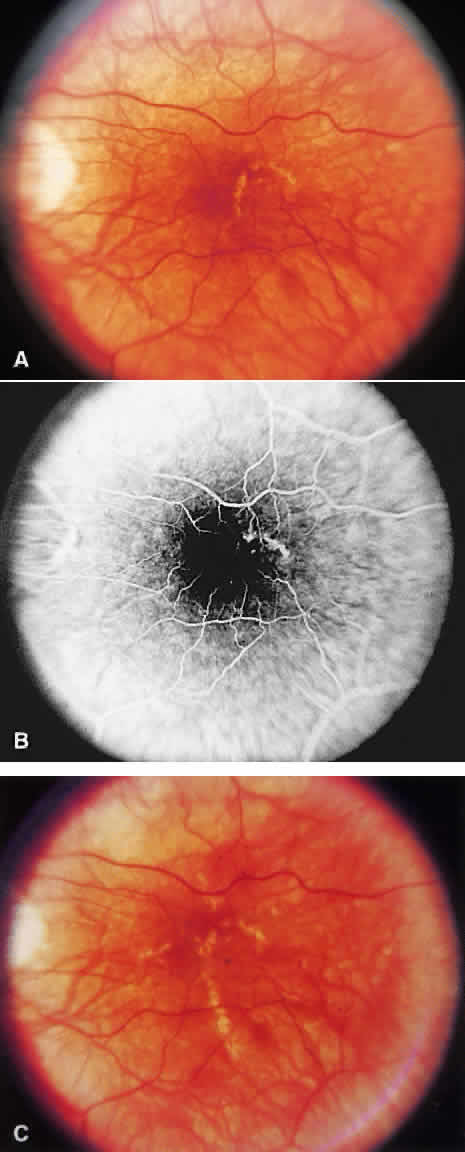

SRNV may be associated with a previous area of histoplasmosis scarring (Fig. 15). The visual prognosis is poorer for eyes with SRNV and a perifoveal choroidal scar in the fellow eye. If such a scar exists, there is a 20% to 25% chance of the development of a neovascular membrane in 5 years; without such scars, there is only about a 4% chance of SRNV developing from the scarring around the disc.102,103 A follow-up evaluation of patients in the MPS showed that choroidal neovascularization is often preceded by an atypical histo spot.104 Macular SRNV, however, has been described in the absence of preceding atrophic scars.105 Prognosis for vision remains good: 81% can be expected to have 20/20 or better acuity after 5 years when the fellow eye has had CNV.104

Fig. 15. A. Histo spots are noted in association with choroidal neovascularization (CNV) membrane (dirty green) and subretinal hemorrhage. B. Corresponding angiogram shows transmitted fluorescence from histo spots, mild peripapillary atrophy, blocked fluorescence from subretinal hemorrhage, and CNV in association with a histo spot. C. After laser treatment to the CNV complex, hemorrhage has resolved and there is early scarring of the CNV membrane. D. Corresponding angiogram shows staining of the scar.